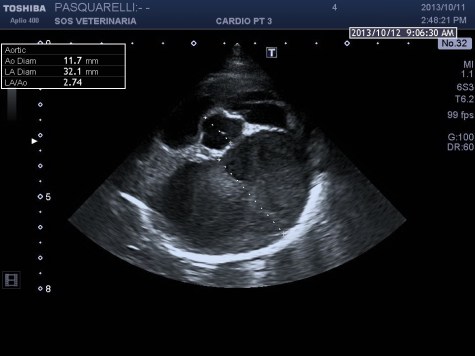

caso di cardiomiopatia ipertrofica del Maine Coone ,presentazione al pronto soccorso tipica con edema polmonare e tromboembolismo aortico completo bilaterale ,per la mia esperienza,nessun trattamento risulta essere efficace per questi soggetti, il decesso avviene nel 90%-95% dei casi e quelli che sopravvivono muoiono nelle settimane successive per le severe complicanze provocate dall’ipoperfusione ,i trattamenti trombolitici non risultano praticabili per diverse ragioni, non ultima quella economica, l’evento drammatico non e’ lo scompenso cardiaco diastolico (sul piano farmacologico gestibile) ma la trombosi aortica spesso anche polmonare .

Per avere una idea del grado di pericolosita’ della malattia basta visionare lo smoke (effetto fumo) nell’atrio sx del soggetto e il voluminoso trombo fluttuante e martellante i lembi valvolari .

Una diagnosi precoce e una corretta terapia antiaggregante avrebbe consentito a questo soggetto di vivere tranquillamente fino allo scompenso congestizio diastolico inevitabile con l’aumentare del grado di ipertrofia.

Il soggetto aveva solo due anni di eta’ e aveva eseguito il test genico risultato negativo , da qui l’importanza, per una corretta analisi cardiologica ,dell’ecocardiogramma ,mai eseguito in questo caso .